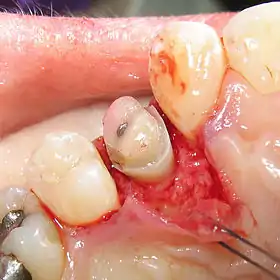

![]() A palatal view of a maxillary premolar during a crown lengthening procedure. | |